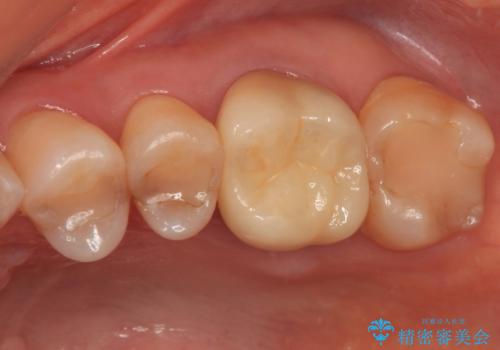

奥歯の被せ物のやり直し 精密根管治療

大きい虫歯 根管治療〜オールセラミッククラウン